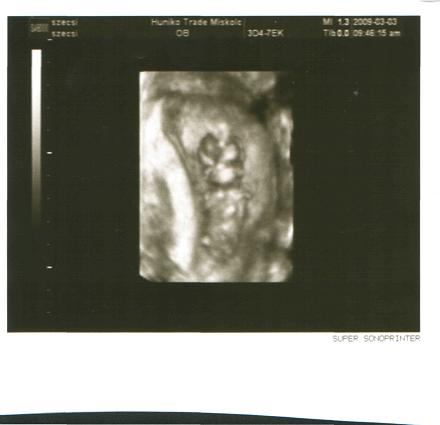

január 14.a terhesség megállapítása a dokinál.

január 14.a terhesség megállapítása a dokinál.

január 24. kórház,az első szívhang hallgatás

január 24. kórház,az első szívhang hallgatás  január 26,mehetek haza 7.hét 2 nap

január 26,mehetek haza 7.hét 2 nap

február 13 péntek,minden ok.hematóma kisebb 9.hét 5 nap

február 13 péntek,minden ok.hematóma kisebb 9.hét 5 nap